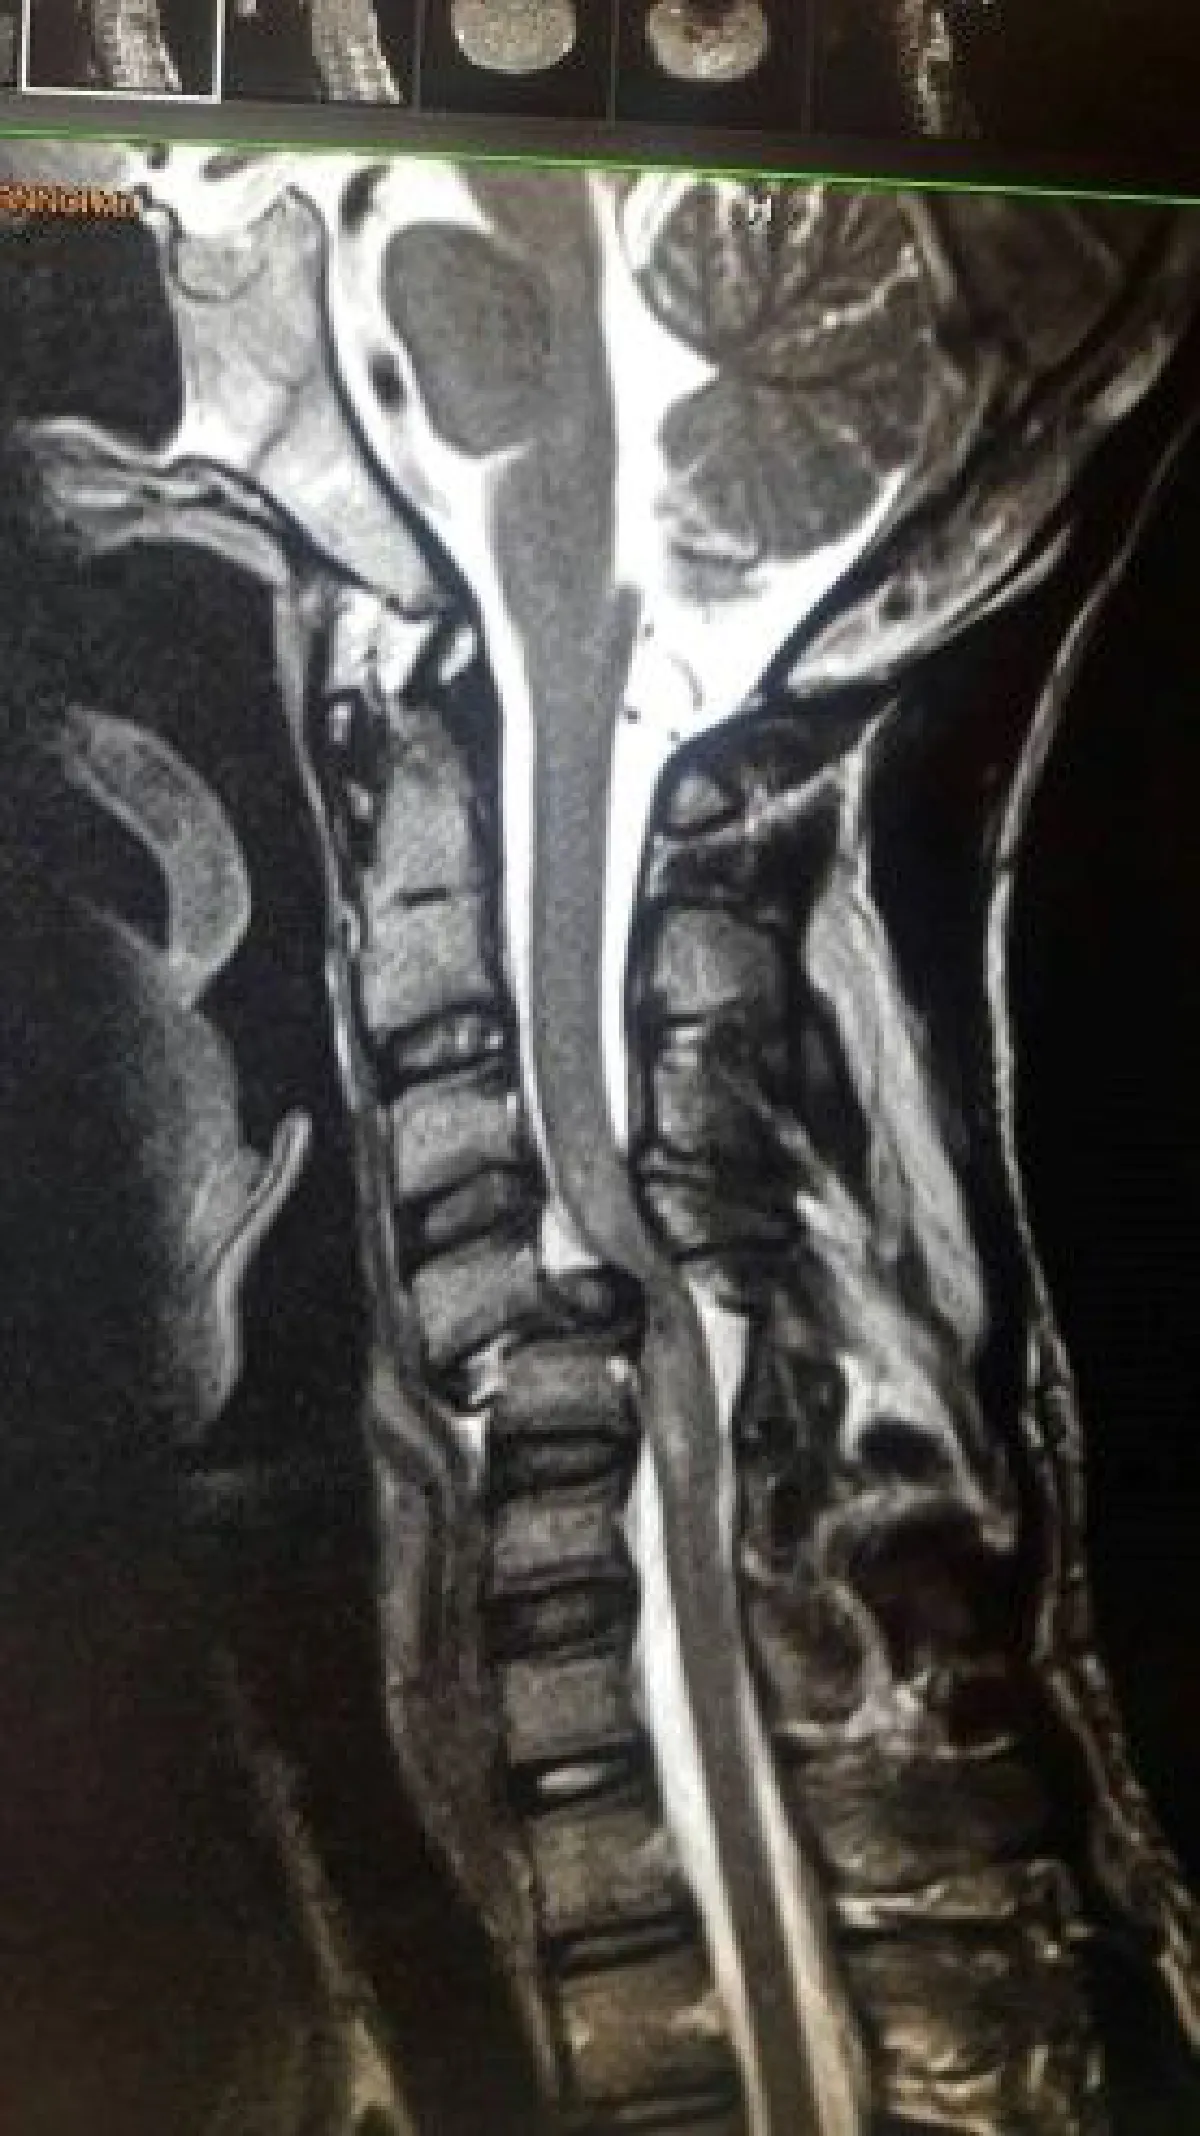

จากกรณีที่โลกออนไลน์เผยแพร่ภาพอันน่าหวาดเสียวของผู้ประสบอุบัติเหตุจากการเล่นเครื่องเล่นสุดฮิตชื่อ "แทรมโปลิน" (TRAMPOLINE) แผ่นกลมๆที่ให้คนขึ้นไปกระโดดเด้งไปมาอย่างสนุกสนาน ซึ่งหากเกิดผิดพลาดขึ้นมาอาจถึงขั้นอัมพาต หรือขั้นเสียชีวิตได้ ดังที่เกิดขึ้นในต่างประเทศ

ล่าสุดเมื่อวันที่ 1 ธ.ค. เพจเฟซบุ๊กชื่อ "ความรู้สนุกๆแบบหมอแมว" ได้โพสต์ให้คำแนะนำเรื่องสิ่งควรรู้ไว้ ก่อให้ลูกเล่นแทรมโปลิน ว่า ปัจจุบัน แทรมโปลิน เป็นอุปกรณ์ที่เริ่มแพร่หลายมากขึ้น เริ่มมีการเอาไปตั้งไว้ในสวนสนุกทั้งในรูปแบบกลมๆ หรือแบบที่เป็นสนามกว้างๆ ซึ่งหลายคนมองว่ามันคืออุปกรณ์ที่น่าสนุกและไม่น่าจะอันตรายอะไร ทั้งที่จริงเป็นเครื่องเล่นที่มีอันตรายได้ในระดับหนึ่งเลย อันตรายในระดับที่ว่าทาง American Academy of Pediatrics เตือนว่าไม่แนะนำให้เด็กเล่นเครื่องเล่นนี้

4. พื้นยางนุ่มๆ แต่ก็เพีงพอที่จะทำให้แขนขาหรือคอหักได้ ถ้าระยะที่ตกลงมาสูงมากพอ